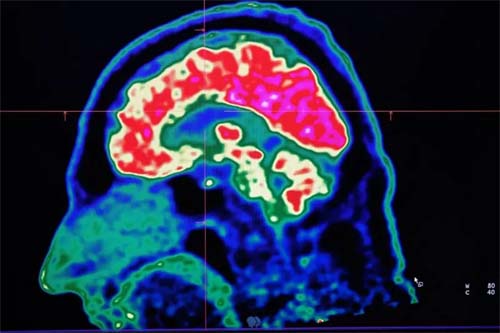

Impactos do Aquecimento Global na Saúde Cerebral e Neurodegeneração

O aumento contínuo da temperatura no planeta tem consequências diretas sobre o funcionamento do cérebro humano, agravando diversas condições neurológicas.

Além disso, as alterações climáticas têm efeitos visíveis no cérebro humano, como evidenciado por dados de ondas de calor em 2023 e 2022, que mostraram um incremento na mortalidade relacionada a fatores neurológicos.

Quanto ao impacto a longo prazo, o calor eleva o risco de agravamento de doenças neurodegenerativas e prejudica a integridade da barreira hematoencefálica, facilitando a entrada de toxinas e agentes infecciosos no cérebro.

Além do impacto físico, ondas de calor podem alterar funções cerebrais, afetando desde a atividade elétrica até a saúde mental, incluindo risco de suicídio, ansiedade e alterações nos medicamentos neurológicos.